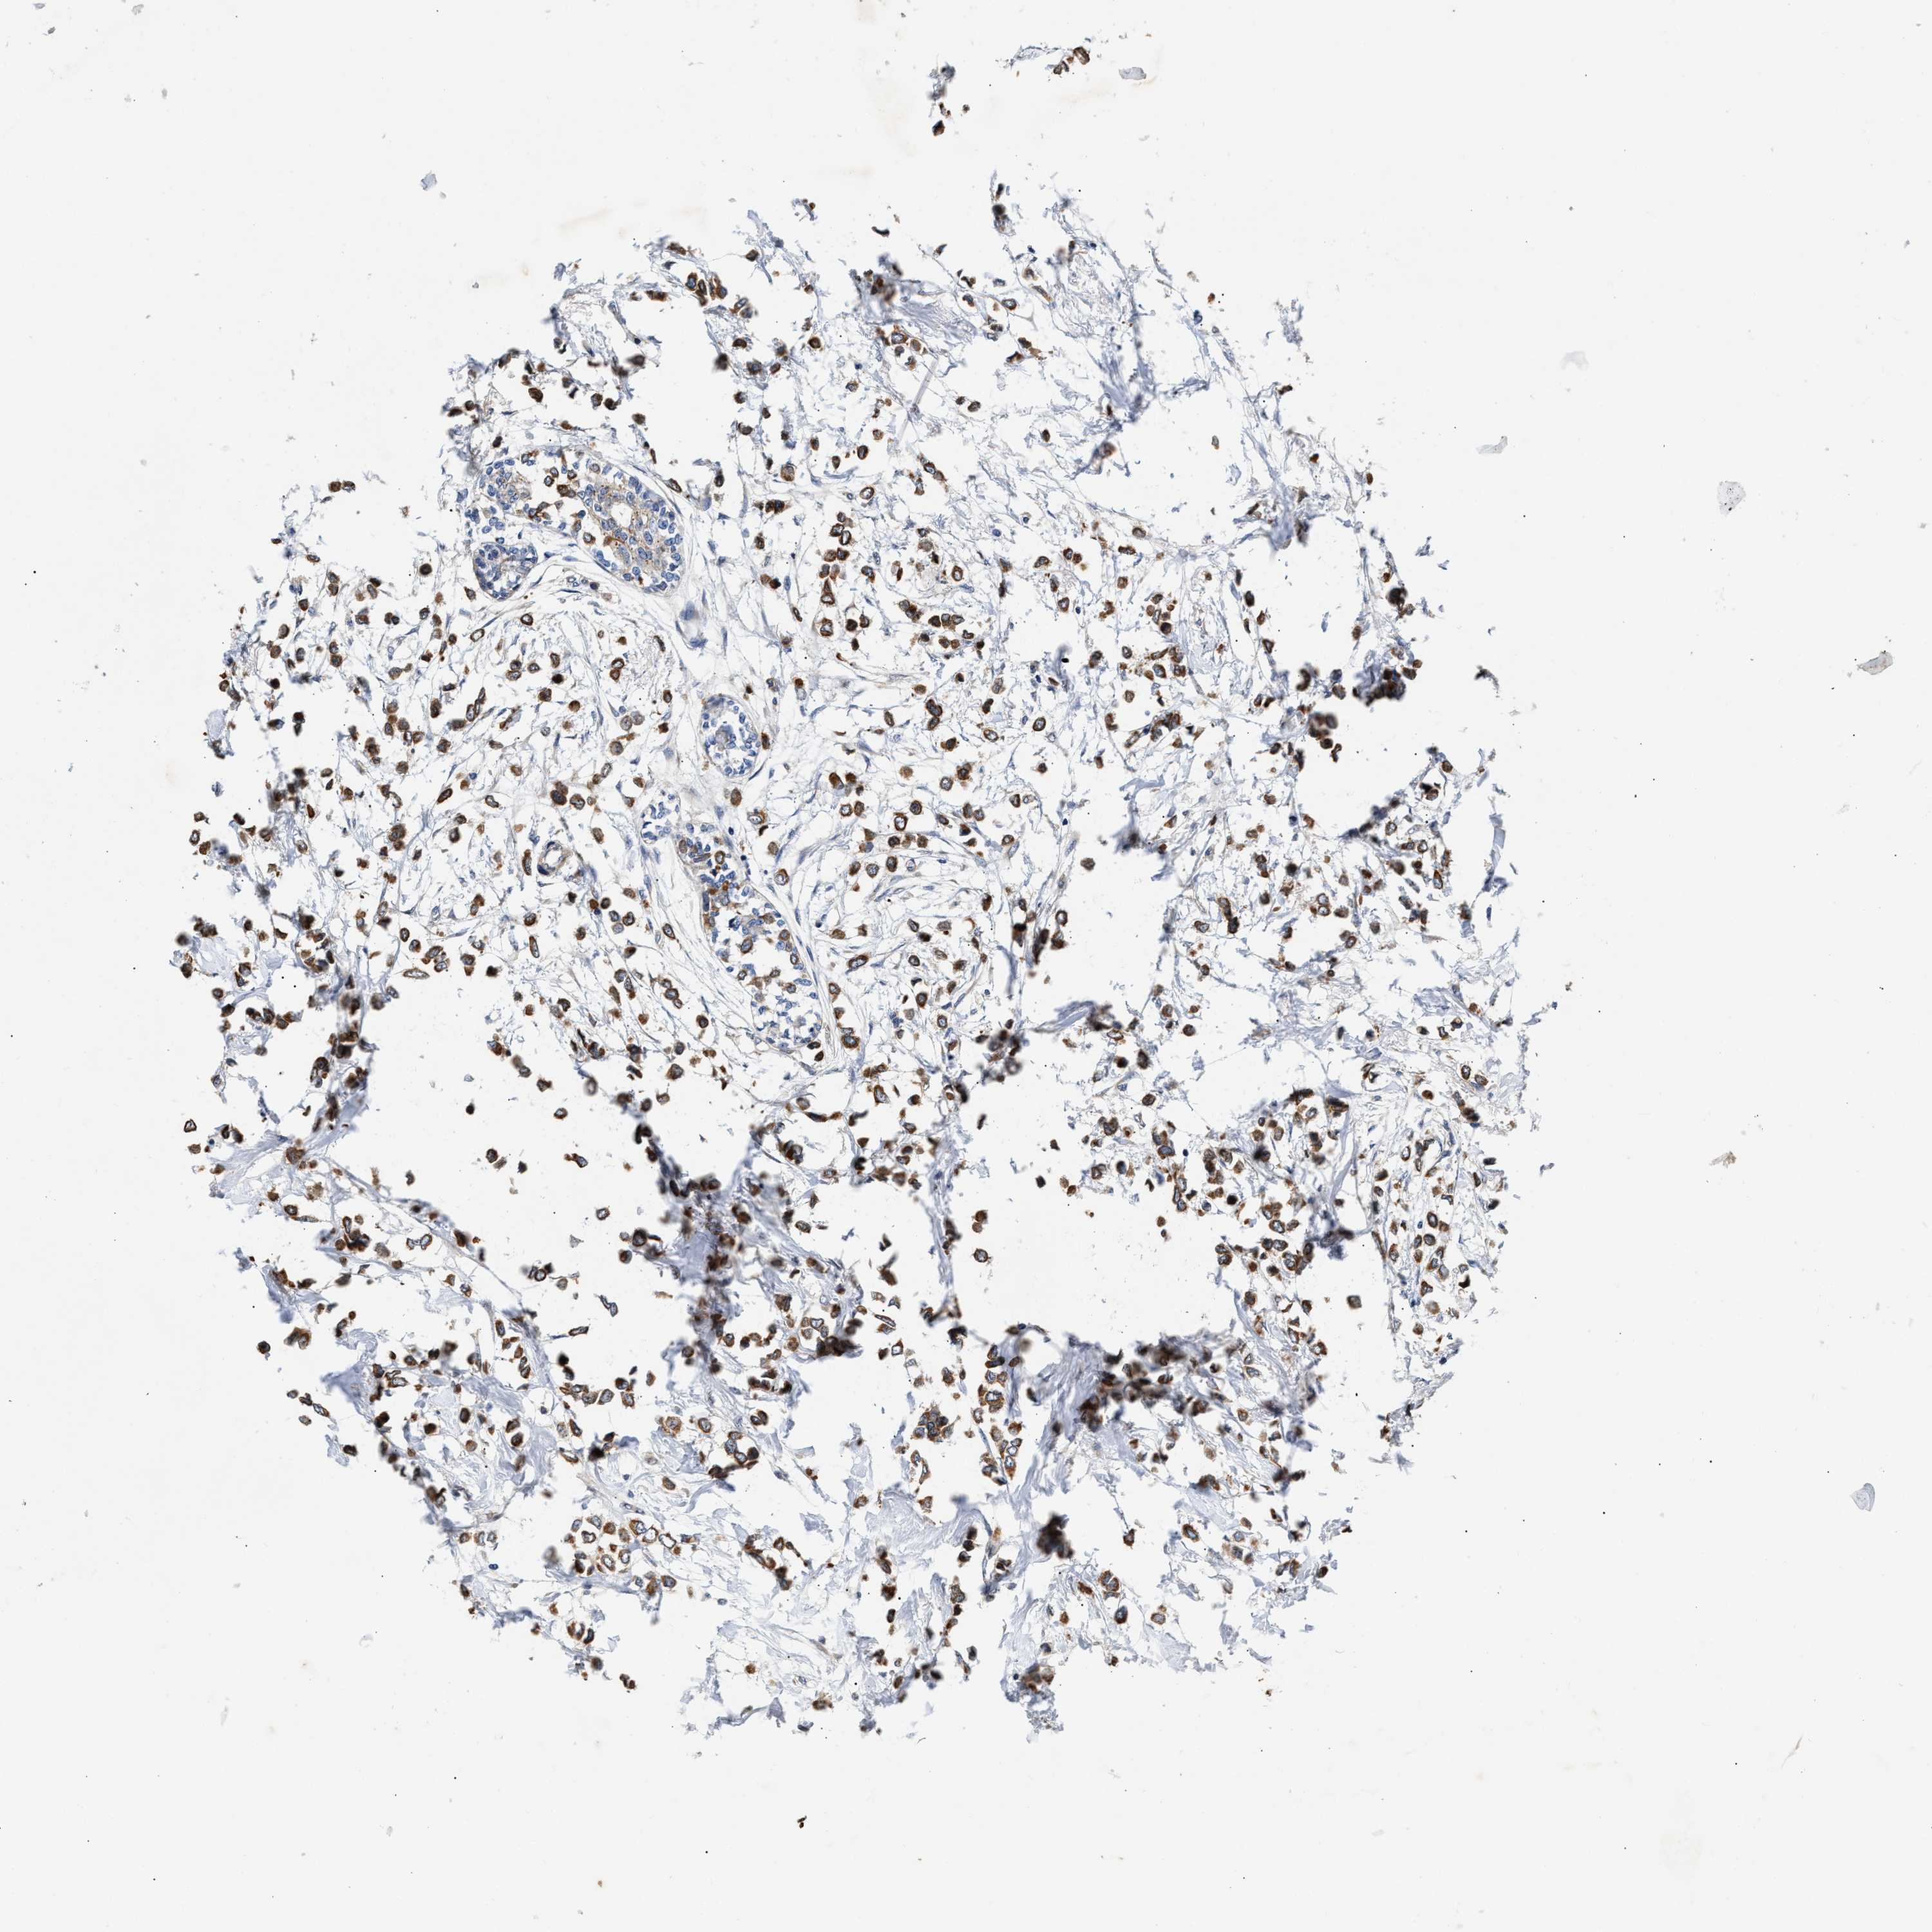

BRCA TCGA BRCA VALIDATION PROTEIN EXPRESSION

ANTIBODIES

AND

VALIDATION